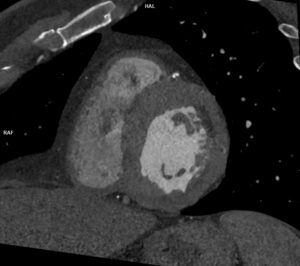

Discuţie caz nr 113: Examinarea angioCT coronariană a fost indicată pentru fenomene de insuficienţă cardiacă și pericardită lichidiană la un pacient cu fibrilație atrială; se remarcă prezența de revărsat lichidian liber pericardic circumferential cu grosime maximă 2 cm în dreptul peretelui liber al ventriculului stâng. Reconstrucția cine evidențiază mișcare paradoxală a septului ce sugerează fiziologie constrictivă.

DE LUAT ACASĂ!!! Calcificările pericardice sunt vizualizate optim cu ajutorul tomografiei computerizate; achiziția angioCT coronariană cu sincronizare ECG evaluează într-o singură investigație: arterele coronare, volumele și funcția ventriculului stâng, poate vizualiza și modificările de cinetică miocardică și caracterizează parenchimul pulmonar, astfel că în pericardită ajută la diagnostic și bilanț etiologic.